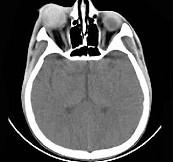

问题 女,24岁,发热畏寒四天,右眼睛疼痛,PE:右眼睑肿胀,结膜充血,伴右眼突出,CT如图所示,应诊断为 ( )

选项 A、眼眶蜂窝织炎 B、眼型Graves病 C、炎性假瘤 D、淋巴瘤 E、Coats病

答案 A